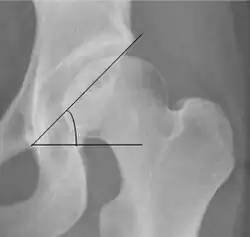

The most useful lines and angles that can be drawn in the pediatric pelvis assessing hip dysplasia are as follows:[3]

• (A) Hilgenreiner line, connects the inferior tips of the iliac bones,[4] at the triradiate cartilage. This line is used to measure the acetabular angle and as a reference for Perkin line.

• (B) Perkin line is perpendicular to Hilgenreiner line, touching the lateral margin of the acetabular roof.[5] This leads to four quadrants and a normal femoral head has to be located in the inferomedial quadrant. We can measure the lateral displacement of the femoral head with regard to the Perkin line by dividing the width of the head that crosses the Perkin line by the diameter of the head. The value for patients under 3 years must be 0 and in older children this ranges from 0 to 22%.

• (D) The acetabular index measures the acetabular roof slope. It is the most useful measure of acetabular dysplasia until 6 years of age. It is formed between Hilgenreiner line and the acetabular roof. In newborns, values of in males and in females are considered normal. It normally decreases with age: